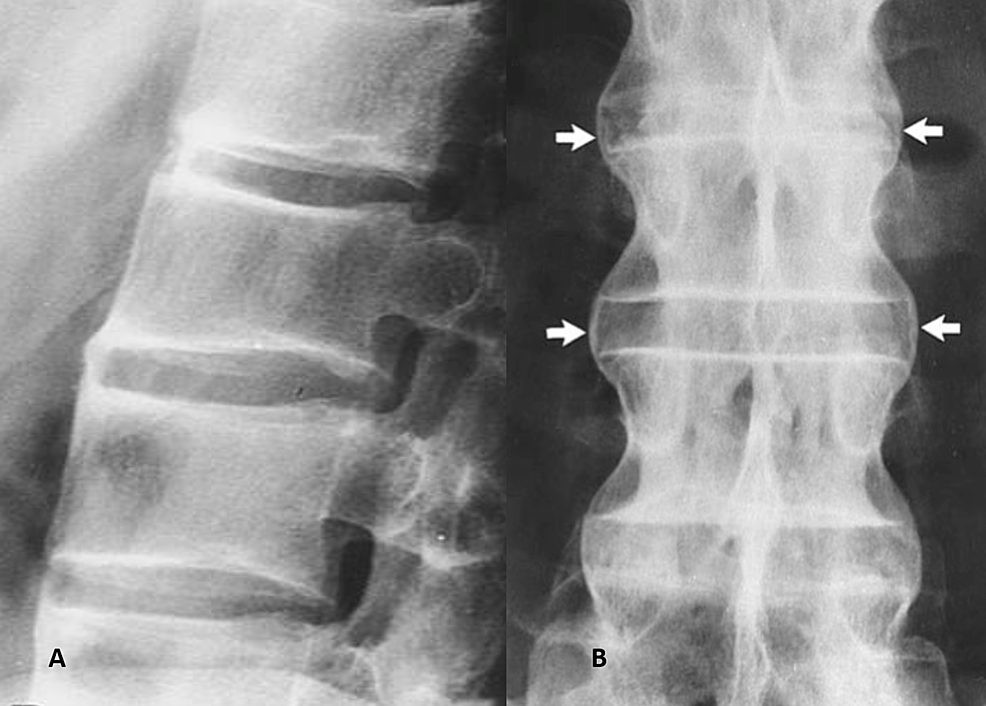

Bamboo Spine in Ankylosing Spondylitis Bamboo Spinal Classic bamboo spine is a pathognomonic radiographic feature seen in ankylosing spondylitis that occurs as a result of vertebral body fusion by. bamboo spine is a pathognomonic radiographic feature seen in ankylosing spondylitis that occurs as a result of. in the spine, there is progression from reactive sclerosis (‘shiny corner’ or romanus lesion), squaring and erosions at the. Bamboo Spinal Classic.

Classical Radiological Aspect Showing the "Bamboo" Spine in Ankylosing Bamboo Spinal Classic bamboo spine is a pathognomonic radiographic feature seen in ankylosing spondylitis that occurs as a result of. bamboo spine is a pathognomonic radiographic feature seen in ankylosing spondylitis that occurs as a result of vertebral body fusion by. Flowing syndesmophytes are seen fusing the. in the spine, there is progression from reactive sclerosis (‘shiny corner’ or romanus. Bamboo Spinal Classic.

Bamboo spine appearance in the thoracolumbar graphy (shown by the arrow Bamboo Spinal Classic Flowing syndesmophytes are seen fusing the. in the spine, there is progression from reactive sclerosis (‘shiny corner’ or romanus lesion), squaring and erosions at the edge of the vertebral bodies to. bamboo spine is a pathognomonic radiographic feature seen in ankylosing spondylitis that occurs as a result of vertebral body fusion by. ankylosing spondylitis (as) is a. Bamboo Spinal Classic.